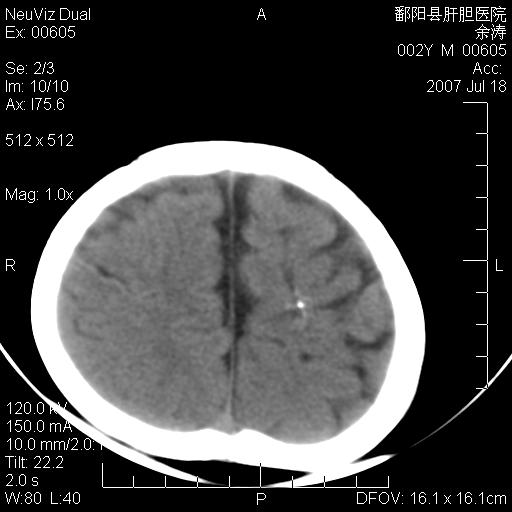

男性 2岁:平时智力障碍。外伤后行颅脑平扫。

2\\结节性硬化

1\\脑裂畸形

2\\血管畸形或错构瘤

3\\透明隔间腔